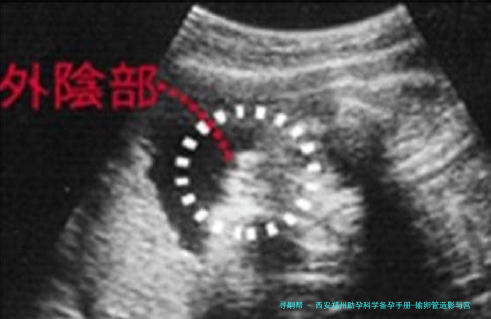

输卵管造影是一种评介输卵管通顺度的影像学检查。它并非将器械深入宫腔,而是通过宫颈向子宫腔体内注入造影剂,然后利用X光或超声技术,即时察看造影剂是否能够顺利通过输卵管并扩散至盆腔,进而评价输卵管是否通畅、阻塞的部位以及子宫腔的样子。

主要目的:其主要功能是诊断输卵管是否通畅,以及是不是存留堵塞、积水或粘连等等问题。它是不育症病因筛查中的重要一环,尤其适合于怀疑因输卵管因素导致不孕的女性。